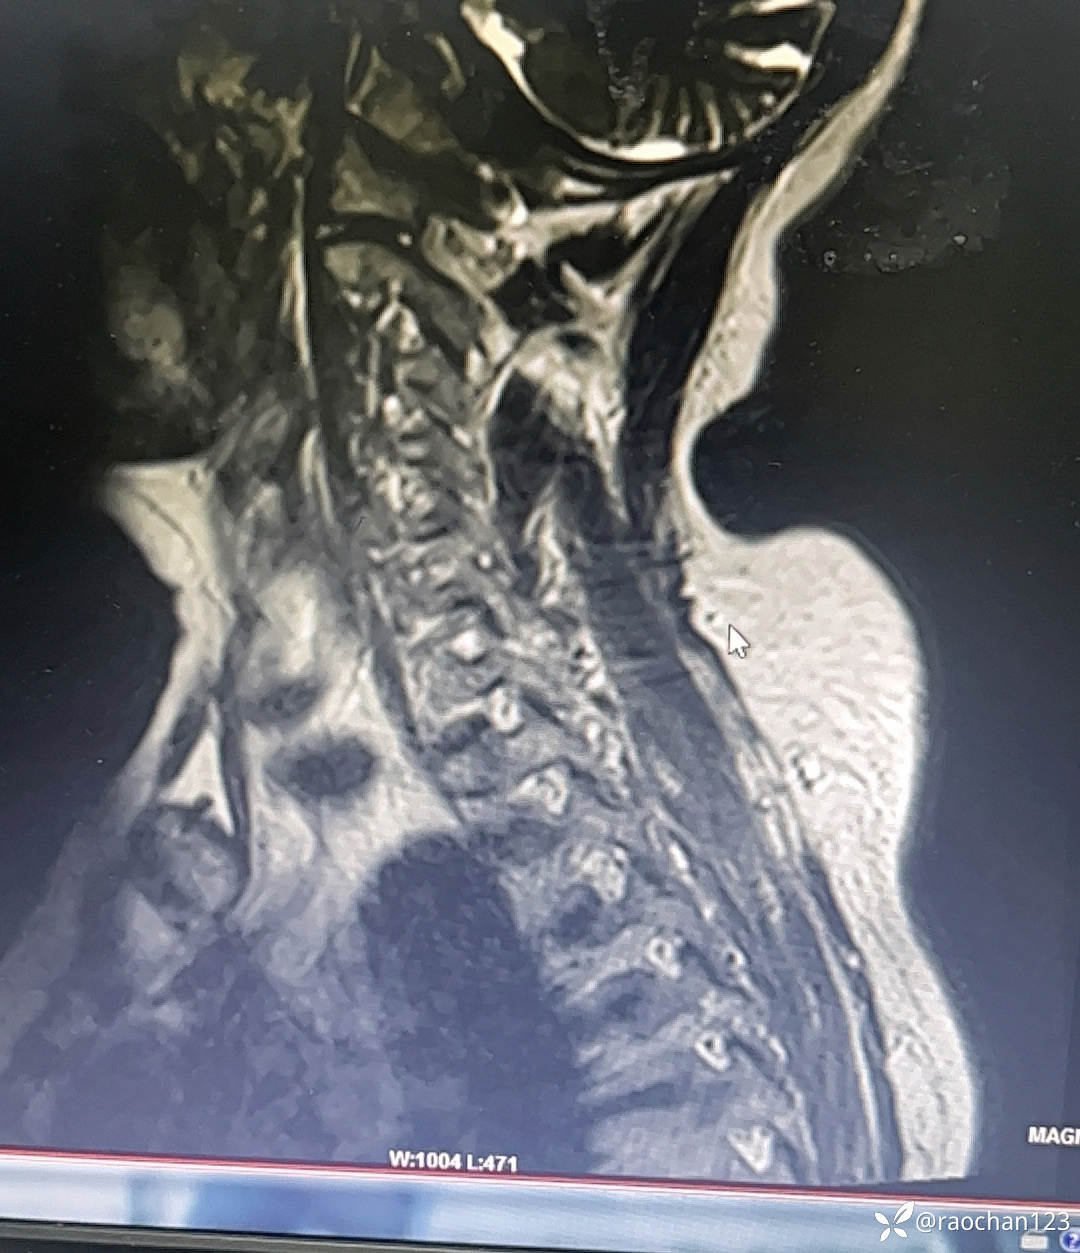

【治疗经过及结果】:给予低流量吸氧,布洛芬混悬液 解热 镇痛,左氧佛沙星抗炎(既往有头孢过敏史)、止痛,热毒宁注射液 清热解毒;艾箱灸、中药塌渍、中药涂擦、火罐、TDP、中药热奄包等中医外治通络祛痛等治疗后,仍有发热,肌酸、肌痛、关节疼痛症状。复查血常规:2024-11-8 13.93# 谷丙转氨酶 45U/L 天门冬氨酸 25U/L 白蛋白 27.0g/L 进一步查乳酸脱氢酶 284U/L 肌酸激酶 26U/L,PCT 0.44ng/ml BNP 811ng/L 免疫五项中IgGA 5.38g/L 血钙 1.94mmol/L 尿微量白蛋白 32.2mg/L 25羟基维生素D 22.68ng/ml 甲胎蛋白、癌胚抗原(-)。颈椎MRI:1.颈椎骨质增生,C4/5、C5/6、C6*7椎间盘轻度突出2、颈后皮下软组织内脂肪堆积,请结合临床。(后颈部皮下软组织内可见异常信号影,T1T2呈高信号,压脂序列呈低信号,颈椎生理曲度变直,椎体后缘连线尚连续,椎体缘骨质光滑,各椎间隙未见狭窄,椎体信号欠均匀,部分椎间盘T2信号减低,C4/5、C5/6、C6/7椎间盘向后轻度突出,硬膜囊轻度受压,椎管无狭窄,黄韧带无肥厚,颈隋未见明显异常)。骨密度:骨质疏松(T值 -4.2)。抗ANA抗体 RF 抗CCP抗体 ENA抗体谱结果待回。患者服用布洛芬混悬液后出现大汗淋漓,血钙偏低,调整为停服布洛芬混悬液、给予醋酸泼尼松10mg 2次/日 口服 解热、抗炎、止痛,金钙尔奇 600mg 2次/日,骨化三醇 0.25ug/日 口服 改善骨质量,暂给予肠内蛋白营养(患者饮食无异常),余治疗同前。